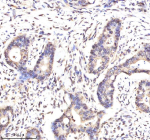

Immunohistochemical staining of Lamin B2 using anti-Lamin B2 antibody. Lamin B2 was detected in a paraffin-embedded section of human colon cancer tissue. Heat mediated antigen retrieval was performed in EDTA buffer (pH 8.0, epitope retrieval solution). The tissue section was blocked with 10% goat serum. The tissue section was then incubated with 2 ug/ml rabbit anti-Lamin B2 antibody overnight at 4oC. Peroxidase Conjugated Goat Anti-rabbit IgG was used as secondary antibody and incubated for 30 minutes at 37oC. The tissue section was developed using an HRP secondary and DAB substrate.